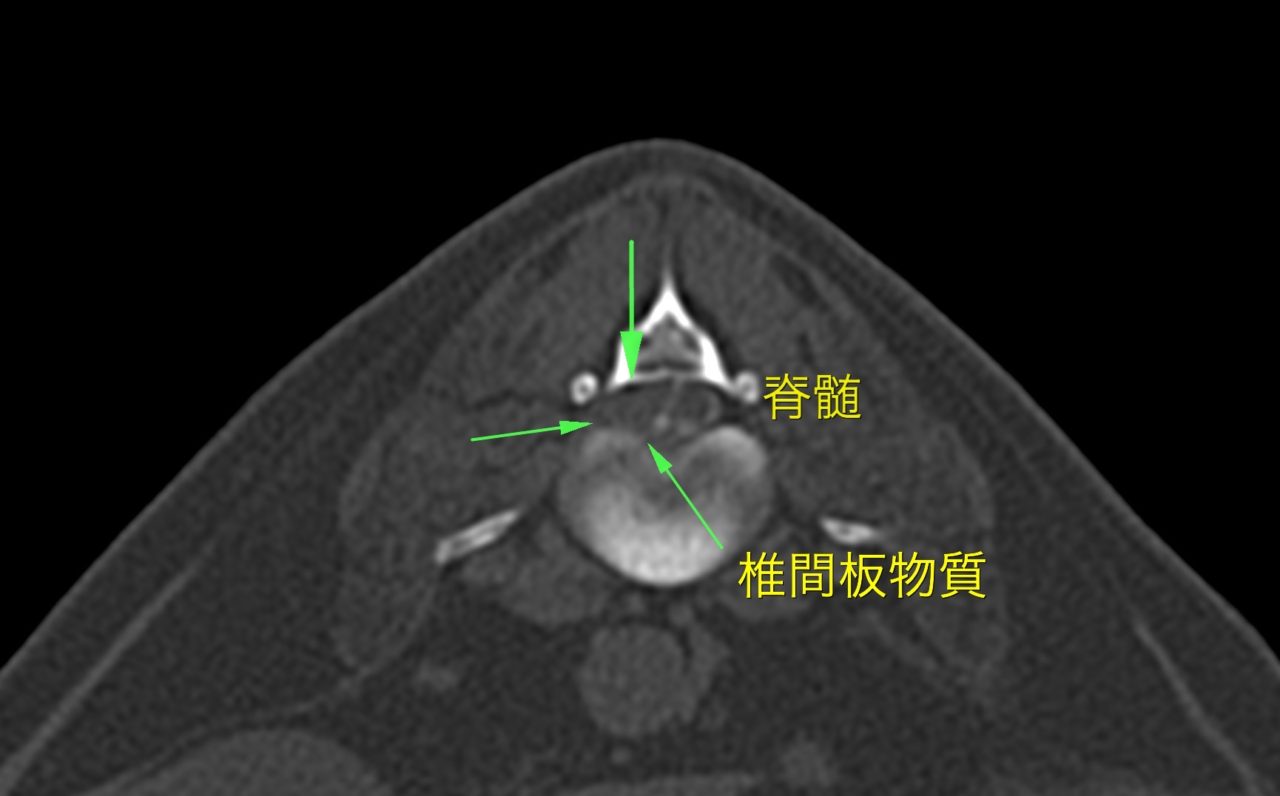

15歳のミニチュア・ダックスさんが急に腰が抜けて、排尿も出来なくなっているのですぐに対応して欲しいと主治医から連絡がありました。かろうじて深部痛覚は残っていました。ご家族は犬が高齢であるため手術は悩まれていましたが、なんとか歩かせて欲しいとの要望があり、短時間で脊髄造影と造影CTを済ませ、そのままL2~L3の脊髄除圧術を行いました。無事にヘルニアを起こしていた椎間板物質も摘除でき、麻酔からの覚醒もスムーズに行われました。高齢のワンコでしたが、よく頑張ってくれました。術後は鍼治療やレーザーなどを行いながら徒手によるリハビリからスタートしていきます。